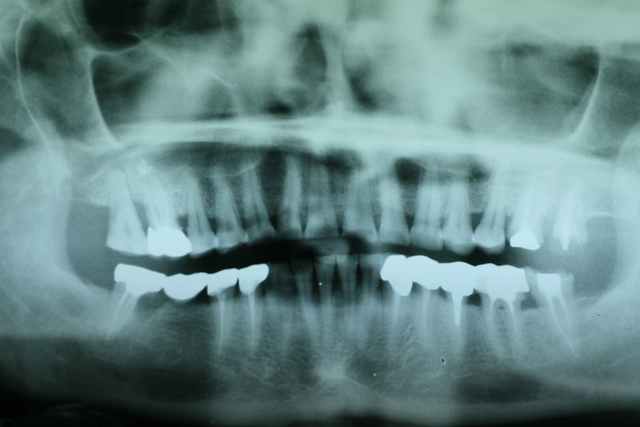

photos et pano du cas initial .

murielle a posté sur un cas de bruxisme en demandant quelle solution envisagée

alors je me lance et propose un cas similaire réalisé en plusieurs étapes ...